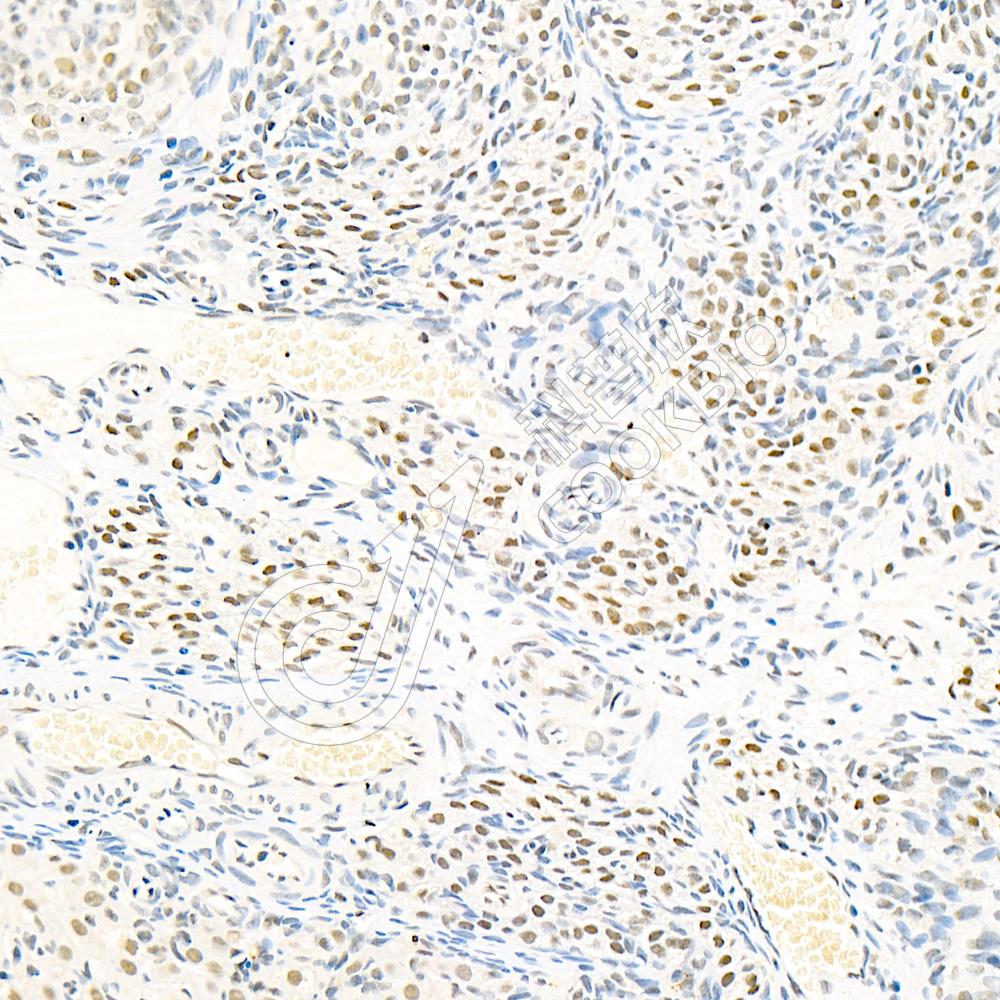

IHC检测RbAp48蛋白(货号 K135907).

样品: 小鼠肾, 4%多聚甲醛 (货号KSG1101) 固定12-24小时.

抗原修复: 柠檬酸抗原修复液(干粉, pH 6.0) (KSG1201), 98℃, 20分钟.

—抗: 1: 1800稀释, 4℃ 孵育过夜.

二抗: S-vision免疫组化多聚二抗(山羊抗兔),即用型 (货号KB3906), 室温孵育20分钟.

样品: 大鼠卵巢, 4%多聚甲醛 (货号KSG1101) 固定12-24小时.